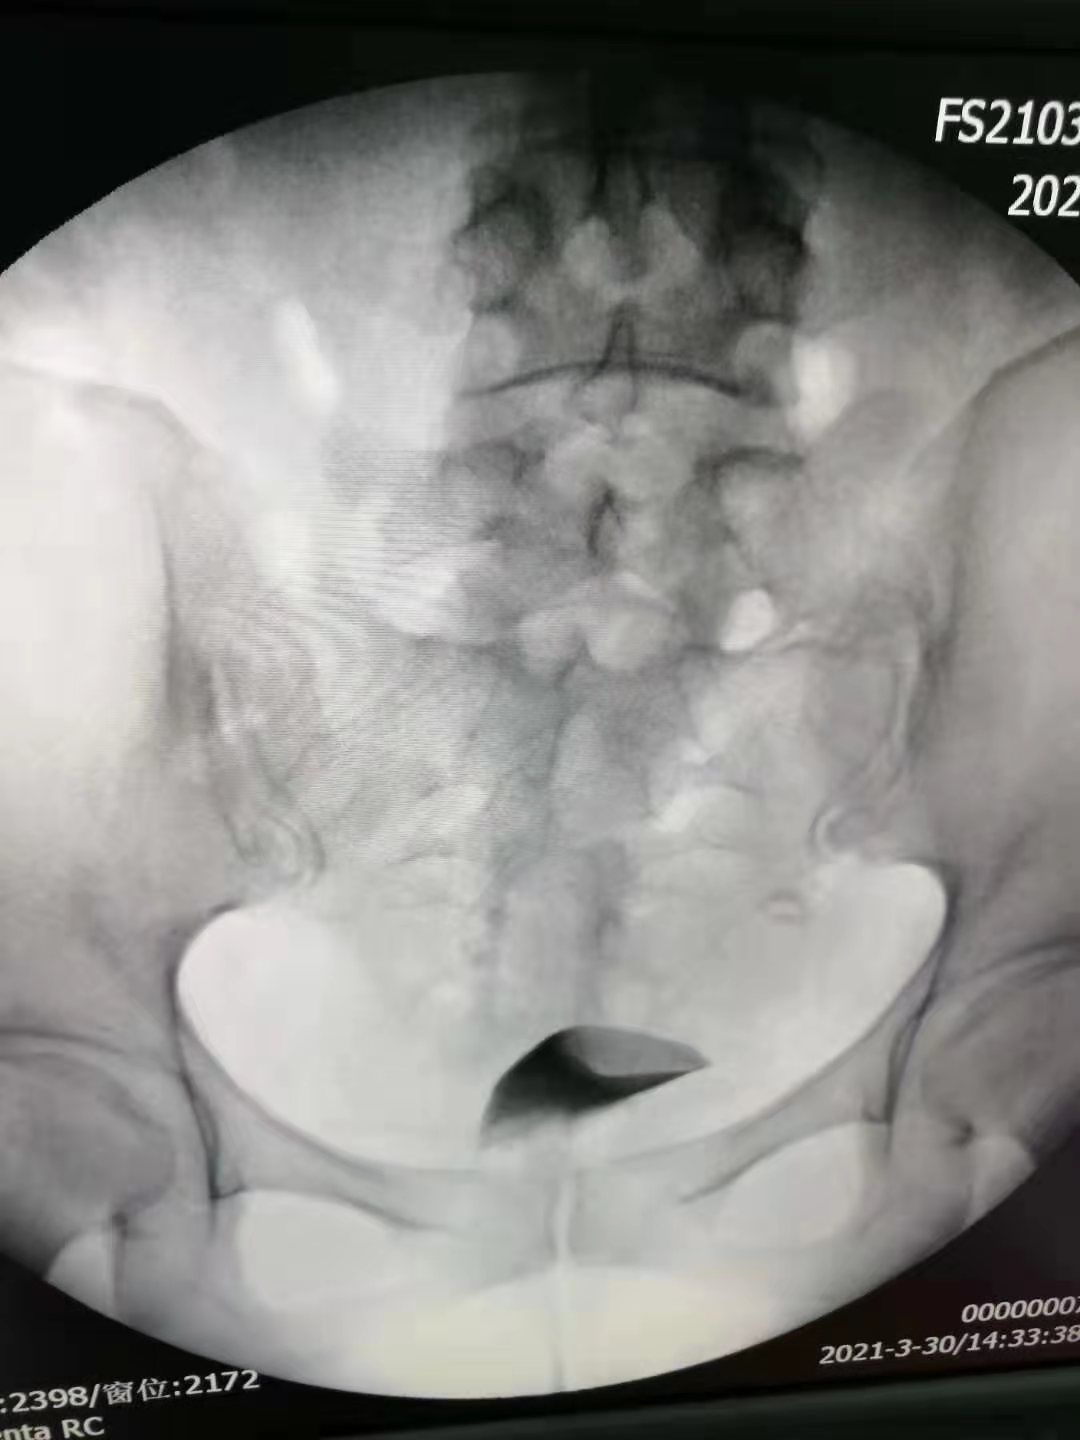

3月30日,我院妇产科成功开展了第一例子宫输卵管造影术。该手术由弋矶山医院生殖中心胡卫华主任专家团队的徐庆阳主任诊疗、余小英博士和我院妇产科医生共同完成。手术过程顺利,术中患者呼吸、心律平稳,无头晕胸闷、恶心呕吐等不适。术中清晰显示了患者子宫腔形态及输卵阻塞部位,从而明确了该不孕症患者的下一步治疗方向。

经X线的子宫输卵管造影术,是通过导管,向宫腔、及输卵管注入造影剂,利用X线诊断仪行X线透视及摄片,根据造影剂在子宫腔、输卵管、及盆腔内的显影情况,来了解输卵管是否通畅、阻塞部位及宫腔形态的一种检查方法。

子宫输卵管造影术损伤小,在有经验的医师操作下,并附以数字X光机的应用,能对输卵管堵塞作出正确诊断,准确率达80%,且具有一定的治疗作用。是用来了解输卵管是否通畅、通畅的程度及具体堵塞部位的最常用的检查方法。